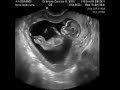

مراحل نمو الجنين

الجنين الحمل سبحان الله مراحل نمو الجنين

شكل الجنين من الشهر الاول لحد الشهر الخامس حقيقي سبحان الله كلنا كنا كده

متى يظهر نبض الجنين اثناء الحمل في السونار حوامل حامل الجنين سونار

الجنين في الأسبوع 16 من الحمل